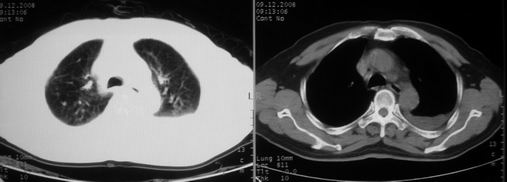

ct左肺下叶大片状高密度影,病变密度不均,界限不清,左侧胸腔积液,治疗后复查临床症状好转而影像学表现病变有发展,还是首先考虑感染性病变,复查时间短附合感染性病变的病理改变。

两肺炎症感染(以左肺下叶为著),双侧少量胸腔积液;建议继续抗炎治疗。